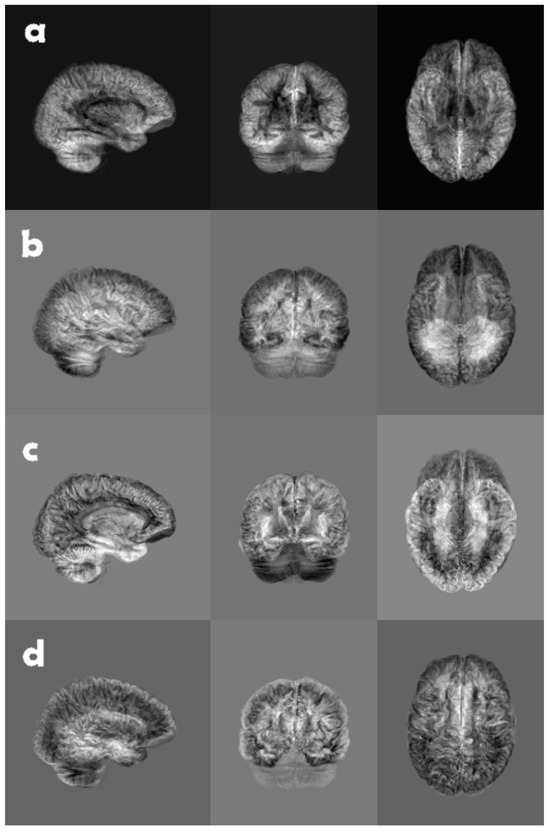

Figure 3. A brain volume of grey matter likelihood, reduced along each coordinate axis, using top (a) mean, (b) standard deviation, (c) skewness, and (d) excess kurtosis. Due to the fact that skewness and excess kurtosis can be both positive and negative in conjunction with the normalization of the grey scale, the backgrounds appear as different shades of grey.

The constant C in (1), in all likelihood, makes little difference to the CNN since it uses several batch normalization layers. It is, however, common for software libraries to include the 3 for kurtosis, thereby making it the so called excess kurtosis, i.e., kurtosis in excess of that of a normal distribution. An example of the different moments is shown in Figure 3.